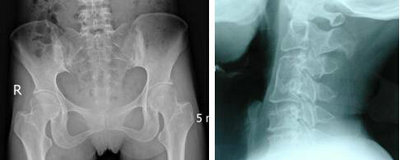

(图:X线片显示其脊椎、髂骨关节遭到破坏)

检查结果:红细胞沉降率增快,达30mm/h,C反应蛋白(CRP)为15.2mg/l;脊椎X线显示其骨质疏松,髂骨关节X线片显示其关节面模糊、局灶性骨质疏松但关节间隙韧带正常。